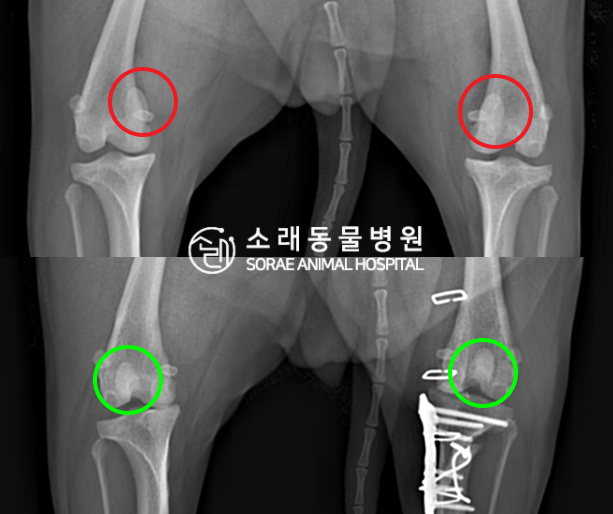

수술전과 수술후에 촬영한 시루의 슬개골

방사선 사진입니다. 나란히 놓고 비교해보니

슬개골의 위치에 확연한 차이가 있는 것을

확인해 볼 수 있는데요. 내측으로 탈구되어 있던

슬개골이 원래 제자리인 활차구에 예쁘게

자리 잡고 있는 모습을 확인할 수 있었습니다.